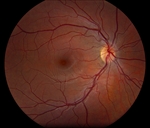

Anterior examination showed clear cornea and posterior subcapsular cataract OU. Dilated fundus examination demonstrated posterior vitreous detachment of the right eye and macular hemorrhage in the left eye. Optic nerves appeared pink and sharp, and the vessels appeared normal. Optical coherence tomography revealed mild irregular foveal contour OD and subretinal choroidal hyperreflective lesion OS.

OCT of the left eye showing a subretinal choroidal hyperreflective lesion. |